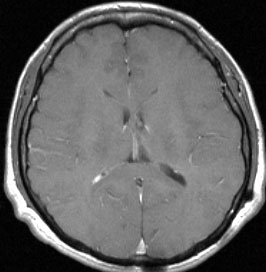

20代の男性の神経細胞腫です。側脳室の中のとても大きな腫瘍です。上段はガドリニウムという造影剤を入れた時のMRIです。下段の中央はCTですが,石灰化が見られます。脳外科の先生には,この脳室内腫瘍は一見transcallosal approach(経脳梁到達法)という手術で取れるように見えるかもしれませんが,そうではなくて,脳室の壁とくに上壁と側壁にくっついているのでなかなか取れません。この患者さんの場合は右の頭頂葉というところからtranscortical approach(経皮質到達法)で全摘出しました。後遺症もなく再発もなく術後10年が過ぎています。全部とれれば治ってしまう腫瘍です。

- CTでは石灰化 (50%) がみれますし,MRIではのう胞が見られて(80%) 造影剤で白く増強(全例)されます

- ほとんどが脳室の前の方でモンロー孔というところの近くにできるのが特徴です

- 頭の中心部にあって透明中隔というところあたりから発生して脳室の壁にベタベタくっついています